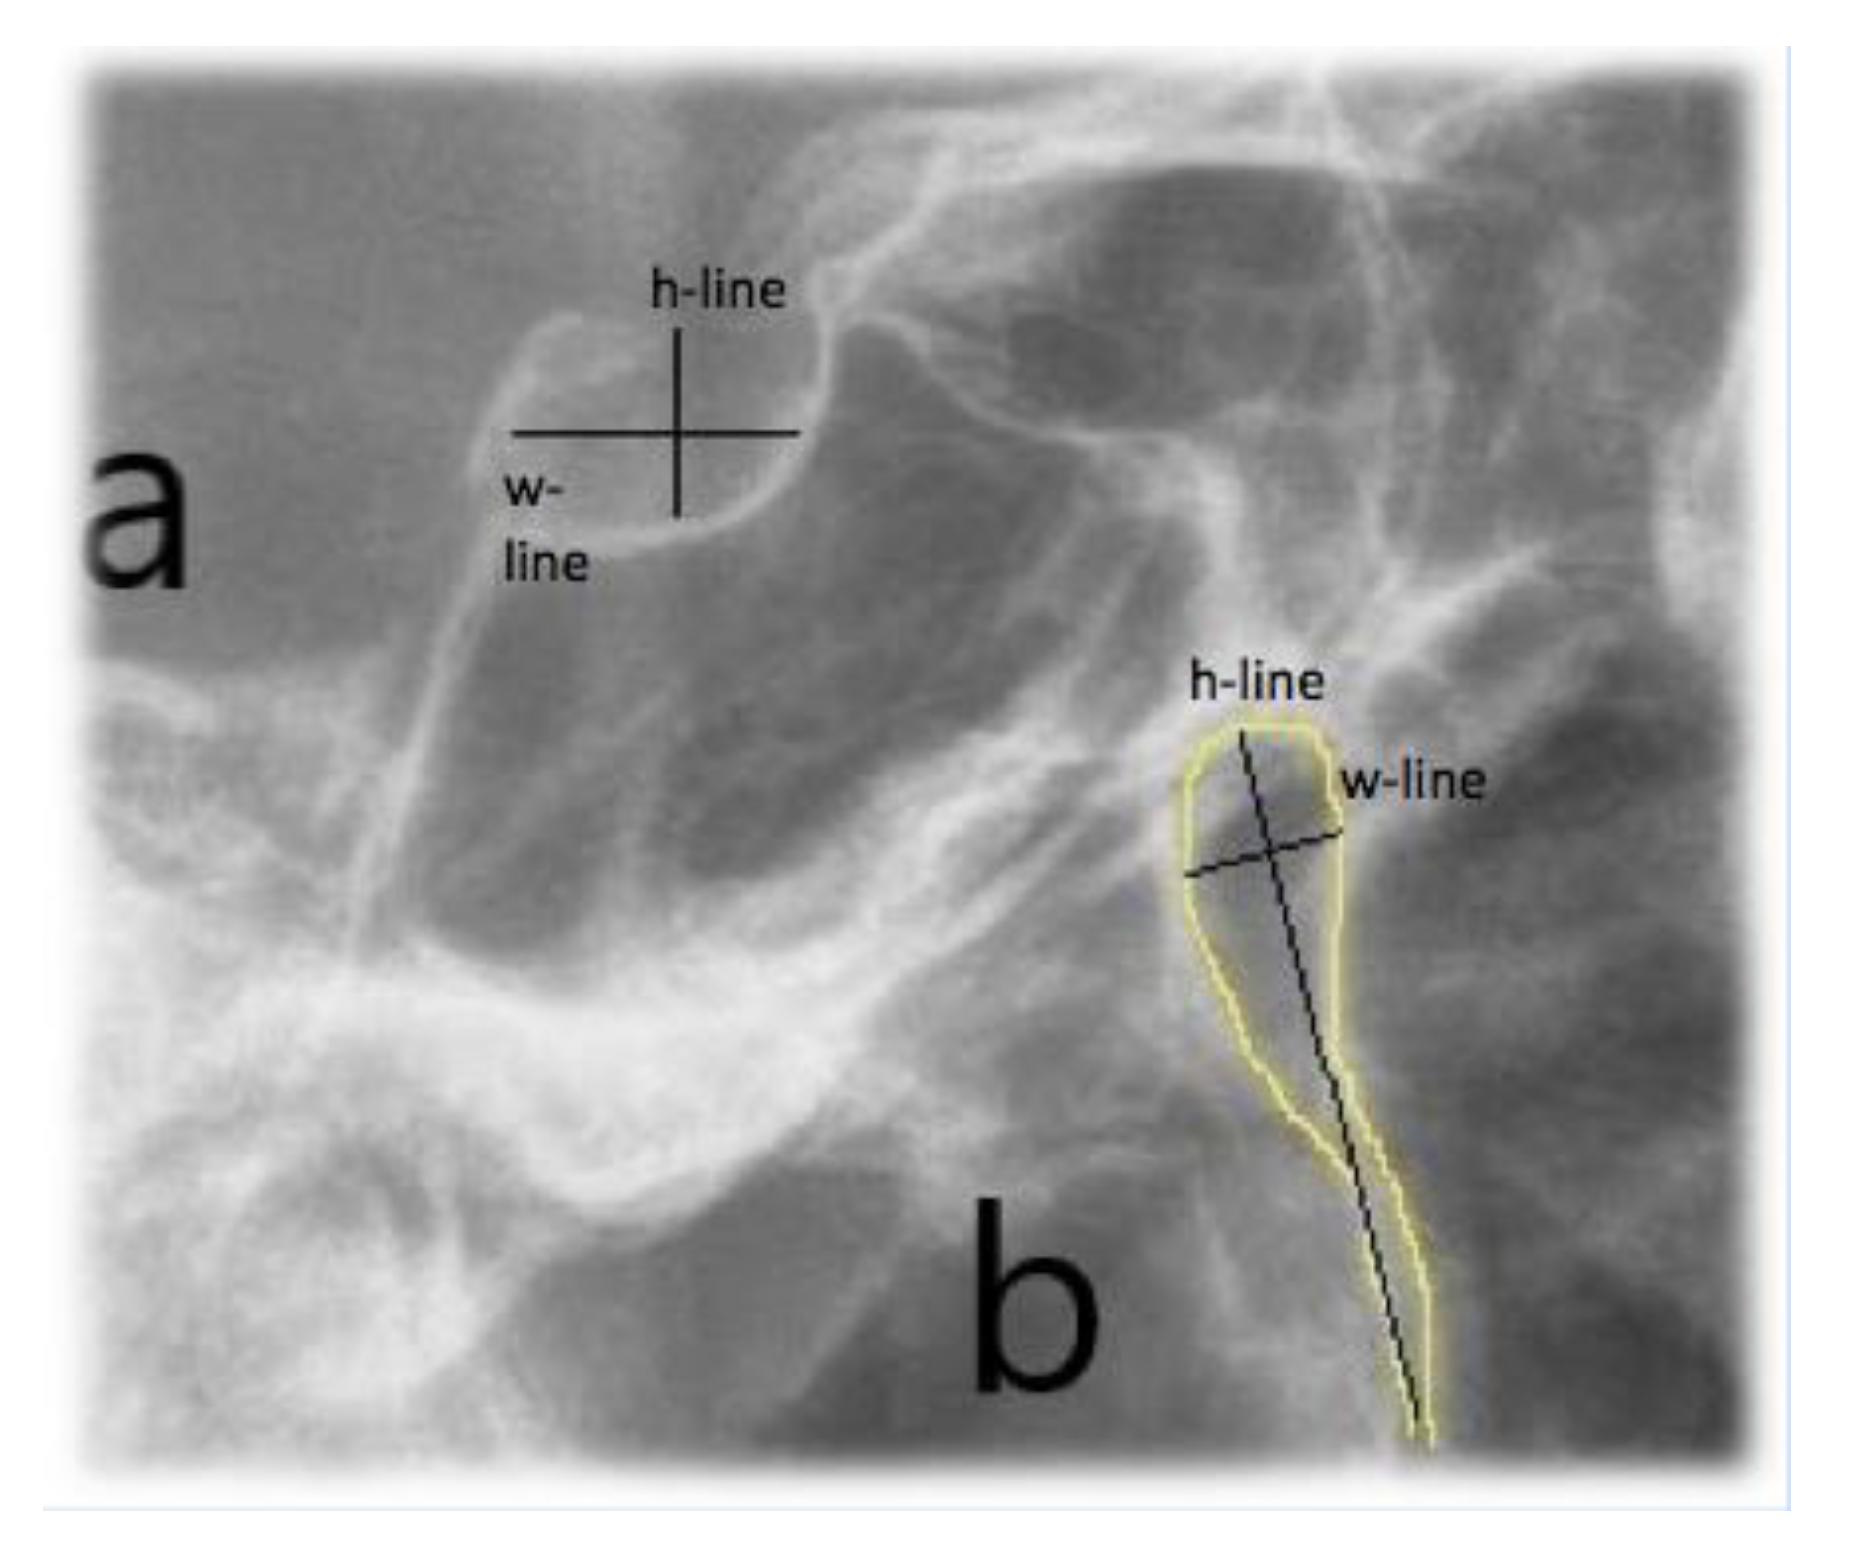

Lateral cephalometric radiographs were used to measure skeletal relationship angle (ANB) and evaluate PP (Figure 1), sella bridging (Figure 2) and atlas posterior arch deficiency (Figure 3).

Sella turcica bridging measurement was performed measuring interclinoidal distance (from the upper portion of sella tuberculum to the sella turcica dorsum) and the greatest distance/diameter between the tip of sella turcica tuberculum and the posterior sellae contour.

The standard scoring scale by Leonardi et al. [7] was used: the absence of bone calcification and sella bridging (type I), partial calcification (type II), complete calcification (type III).

Figure 2. Full sella bridging.